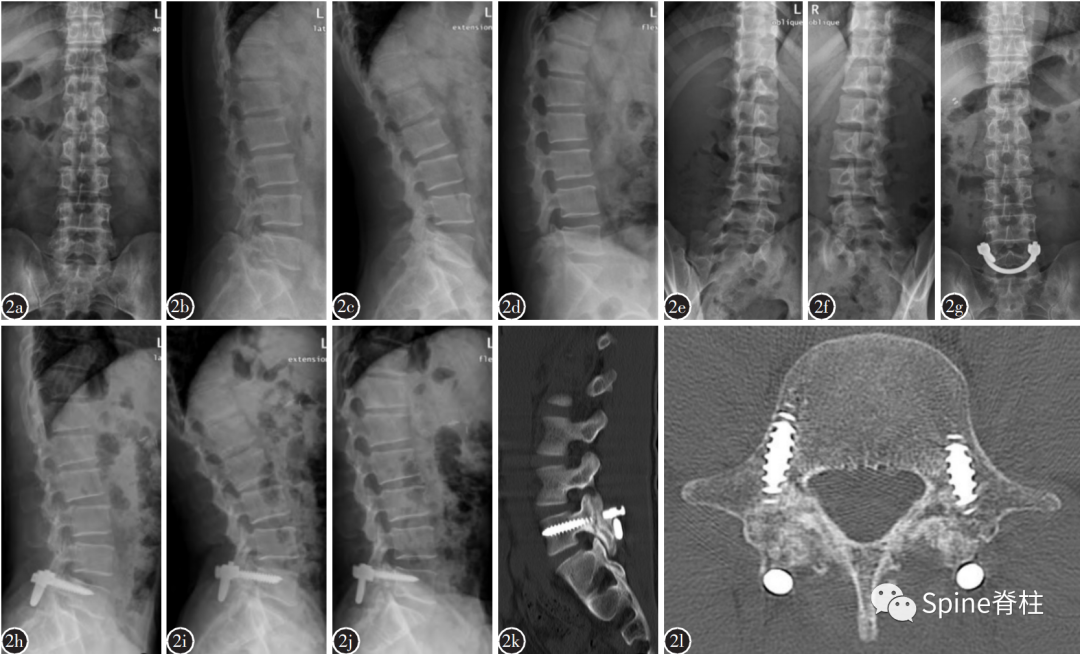

2019年国内解放军总医院第七医学中心李放教授团队。根据临床特点和影像学表现将所有病例分为3型:

• A型为单纯型峡部裂,无椎间盘突出及腰椎滑脱;

• B型为峡部裂伴有轻度椎间盘突出或I度滑脱,无神经压迫症状及体征;

• C型为峡部裂合并I度或Ⅱ度滑脱并椎间盘突出同时有神经压迫症状及体征。

并建议保守治疗无效的青年战士A、B型腰椎峡部裂病例采用椎弓根螺钉固定,峡部自体髂骨原位植骨融合率高,效果好,C型战士峡部裂则宜采用后路椎间植骨融合椎弓根螺钉内固定术。